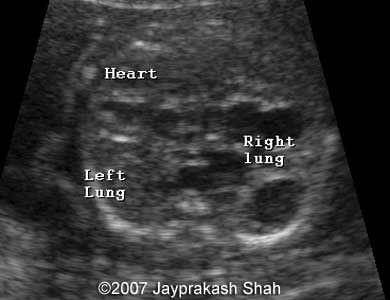

15. Paru-paru

Sudah mendekati akhir dari tahap pertumbuhan. Paru-paru adalah organ terakhir yang berkembang dengan sempurna. Alasannya, organ tersebut sebenarnya tidak terlalu penting untuk fetus yang bernapas dalam cairan ketuban.

Sel pembentuk paru-paru mulai memproduksi zat surfactant yang mampu memperbesar diri di minggu ke-23. Ini akan mempersiapkan fetus untuk menghadapi dunia luar.